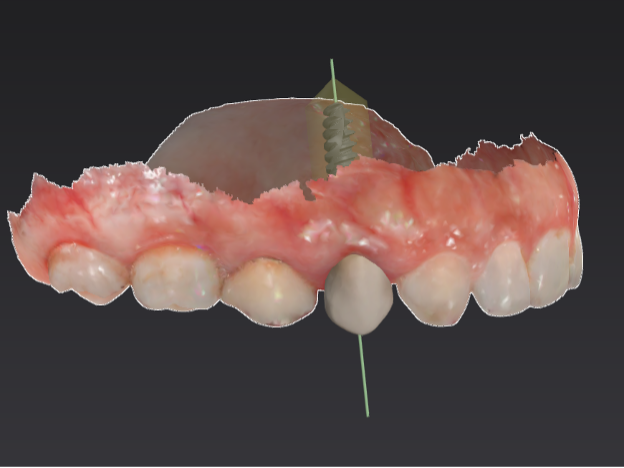

The 3D image we took during your consultation is used to create computer-aided guidance with our sophisticated X-Nav system. Visualizing the placement of your dental implants in 3D eliminates guesswork and potential complications. In the skilled hands of Dr. Peterson, proper planning combined with X-Guide Dynamic 3D Navigation during surgery elevates surgical excellence while increasing efficiency and safety. If you received full-mouth dental implants, our customized, streamlined protocol enables Dr. Peterson to fit you with temporary 3D-printed teeth within 24 hours of your surgical procedure.

3D planning

Planning detail

Additional planning view